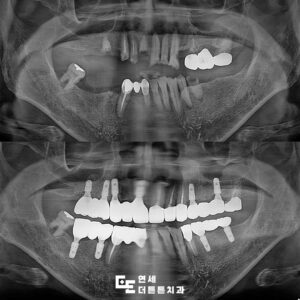

환자분께서는 보철물의 형태와 색상에

만족감을 표시하셨으며 저작 기능도

편하시다고 하였습니다.

더불어 6개월 검진 시에도 주변 골 소실 없이

양호한 상태가 유지되고 있었습니다.